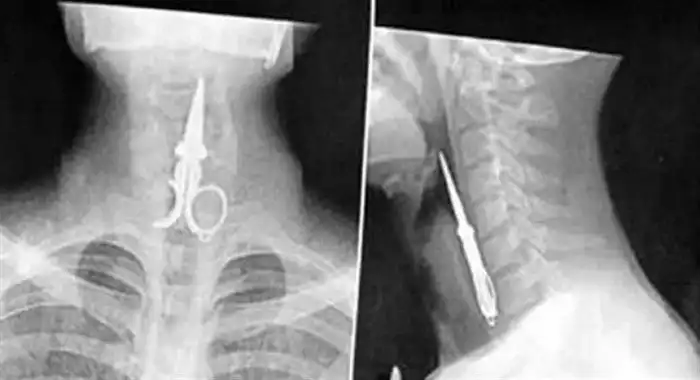

И снова о ножницах. Это человек пытался использовать их как зубочистку. Вышло, как видите, неудачно.